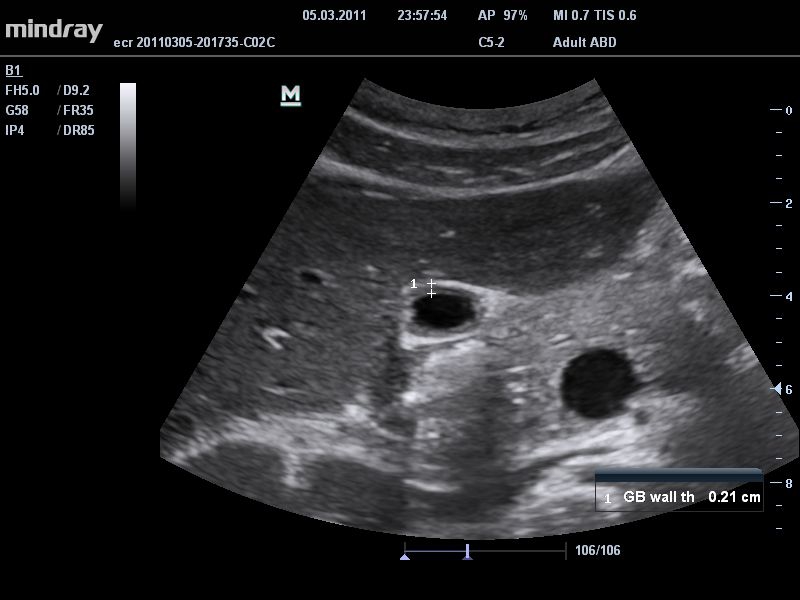

Ультразвуковая система Mindray DC-T6 – это инновационный аппарат для проведения высокого уровня диагностики с качественной визуализацией и широким спектром применения. Платформа рекомендована для использования в коммерчески многопрофильных медицинских учреждениях и государственных лечебных клиниках.

Система сочетает в удобном и компактном корпусе не только традиционные возможности современного УЗИ-сканера, но и инновационные технологии, повышающие точности диагностики состояния пациентов.

• THI со сдвигом фазы: увеличивает четкость визуализации желчного и мочевого пузыря и повышает отношение сигнал-шум.